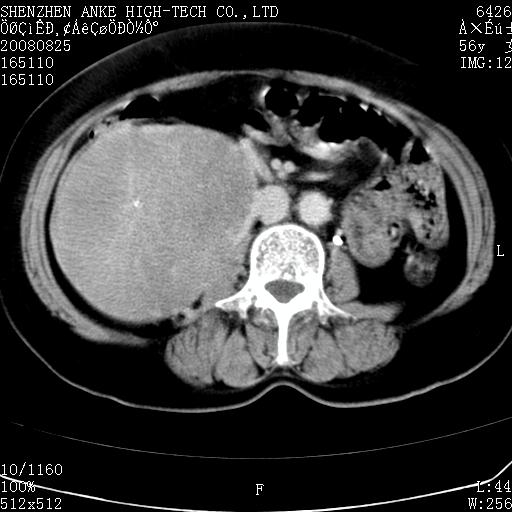

患者,女性,56岁,腰痛3年,查:右腹部约8x10cm肿块,固定,无压痛;8月23日在外院做了平扫,发现右肾巨大肿块(外院具体诊断不祥);今天在我院做了静脉肾盂造影,示:右肾明显增大,分泌功能明显减弱。

1)考虑右肾癌并右肾静脉瘤栓形成。2)脂肪肝。